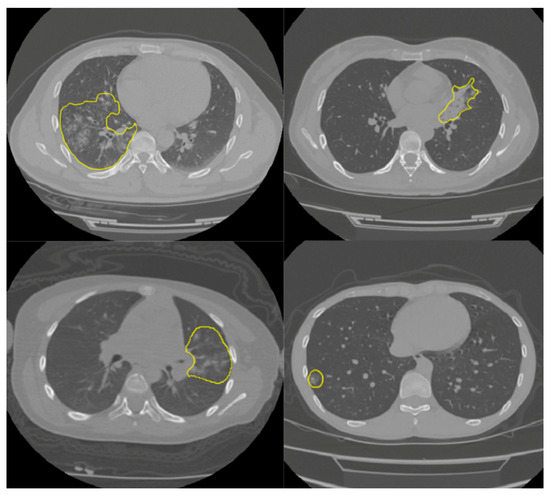

2.1. Dataset

- CT Images in COVID-19—The Cancer Imaging Archive (TCIA) Public Access—Cancer Imaging Archive Wiki. Available online: https://wiki.cancerimagingarchive.net/display/Public/CT+Images+in+COVID-19#702271074dc5f53338634b35a3500cbed18472e0 (accessed on 25 March 2021).

- Tsai, E.B.; Simpson, S.; Lungren, M.P.; Hershman, M.; Roshkovan, L.; Colak, E.; Erickson, B.J.; Shih, G.; Stein, A.; Kalpathy-Cramer, J.; et al. The RSNA International COVID-19 Open Radiology Database (RICORD). Radiology 2021, 299, E204–E213. [Google Scholar] [CrossRef]